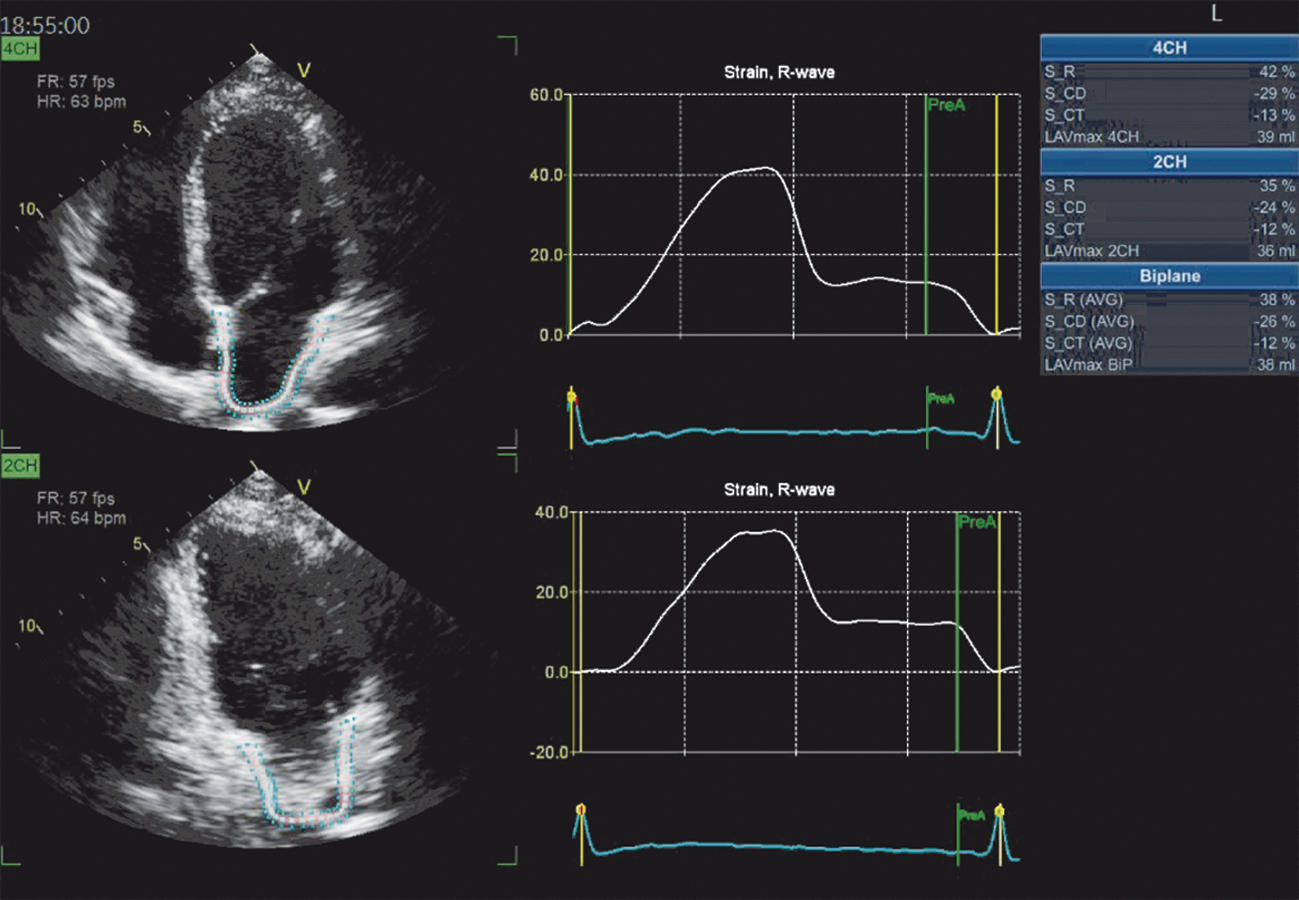

A avaliação da deformação atrial identifica os três componentes da função atrial, que incluem a fase de reservatório, a de conduto e a de contração (figuras 1 e 2). A fase do reservatório corresponde à capacidade do átrio esquerdo de acomodação do sangue das veias pulmonares durante a sístole ventricular.

Figura 1. Exemplo de análise da função do átrio por meio da medida do strain atrial, com uso de software dedicado, em um indivíduo normal. SR: tensão de reservatório; S CD: tensão de condução; S CT: tensão de contração; 4CH: corte de quatro câmaras; 2CH: corte de duas câmaras; LAVmax: volume máximo do átrio esquerdo; BIP: valor das medidas considerando os dois planos.

A fase de condução, por sua vez, diz respeito ao esvaziamento passivo do átrio, que contribui para o enchimento ventricular na protodiástole. Já a fase de contração mostra o átrio esquerdo se contraindo ativo, o que contribui para o volume telediastólico ventricular.